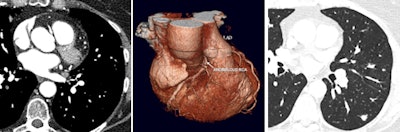

A case in point, van Beek remembers a CT scan that showed a right coronary artery anomaly (shown in figure below). He insisted on a reconstructed full field-of-view and discovered metastatic breast cancer, which changed management of the patient to extensive chemotherapy before coronary surgery. This also led to a shift in the cardiologist's mind at the time as to the usefulness of reconstructed full field-of-view images.